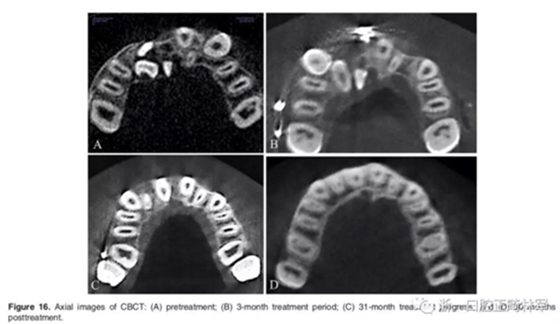

影像學(xué):頭顱側(cè)位片示:矢狀向和垂直向骨骼發(fā)生變化(ANB角,3°;SN-MP,51°);上頜切牙略前傾(U1-SN,106°),與下頜切牙一致(IMPA,75°);病人的面部輪廓得以保持。全景片示:由于牙齒萌出,上前牙區(qū)垂直向牙槽骨水平增加;雖然前牙牙根較彎曲,但其平行度仍可,且無明顯的牙根吸收。CBCT示:前牙唇側(cè)骨質(zhì)連續(xù)性改善,牙根唇側(cè)支持組織變好,牙槽骨高度、厚度均有增加,但轉(zhuǎn)矩的改變一定程度上導(dǎo)致了局部應(yīng)力的增大。

2年隨訪:咬合關(guān)系保持穩(wěn)定,無明顯復(fù)發(fā),下頜有一定晚期生長趨勢;前牙牙齦外形、牙冠高度無明顯變化;唇側(cè)牙槽骨高度、厚度均保持良好。